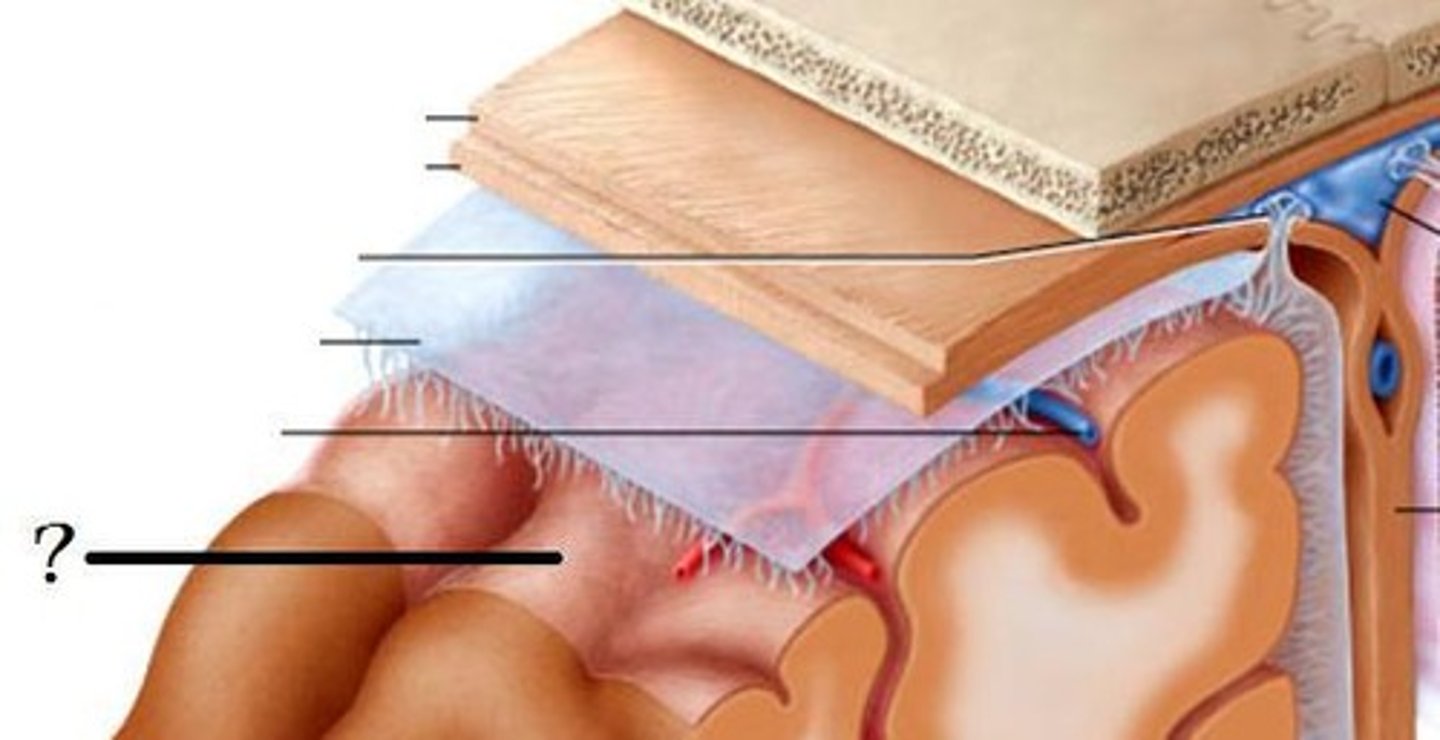

Dura mater

What is this?

Arachnoid mater

What is this?

pia mater

What is this?